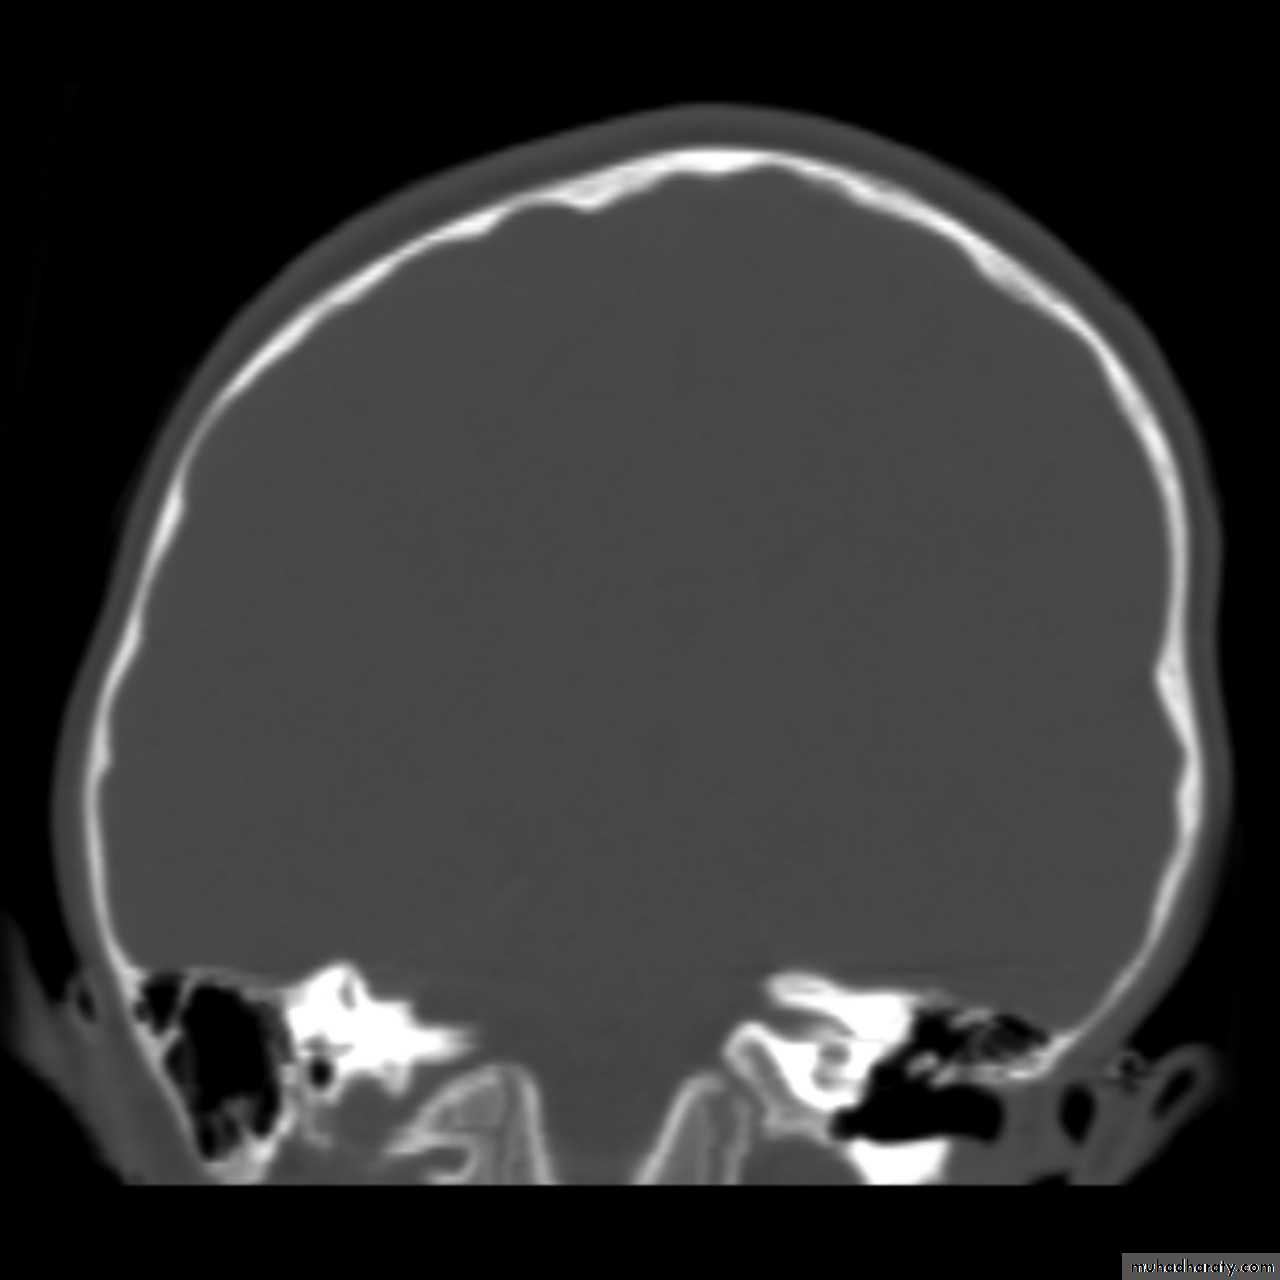

Skull X-ray findings in increased intracranial pressure

• Sutural separation in children.

• ‘Copper-beating’ marking of the cranial vault.

• Thinning of dorsum sellae.

• Erosion of the posterior clinoid process.

Copper-beating’ marking

Neuro surgery